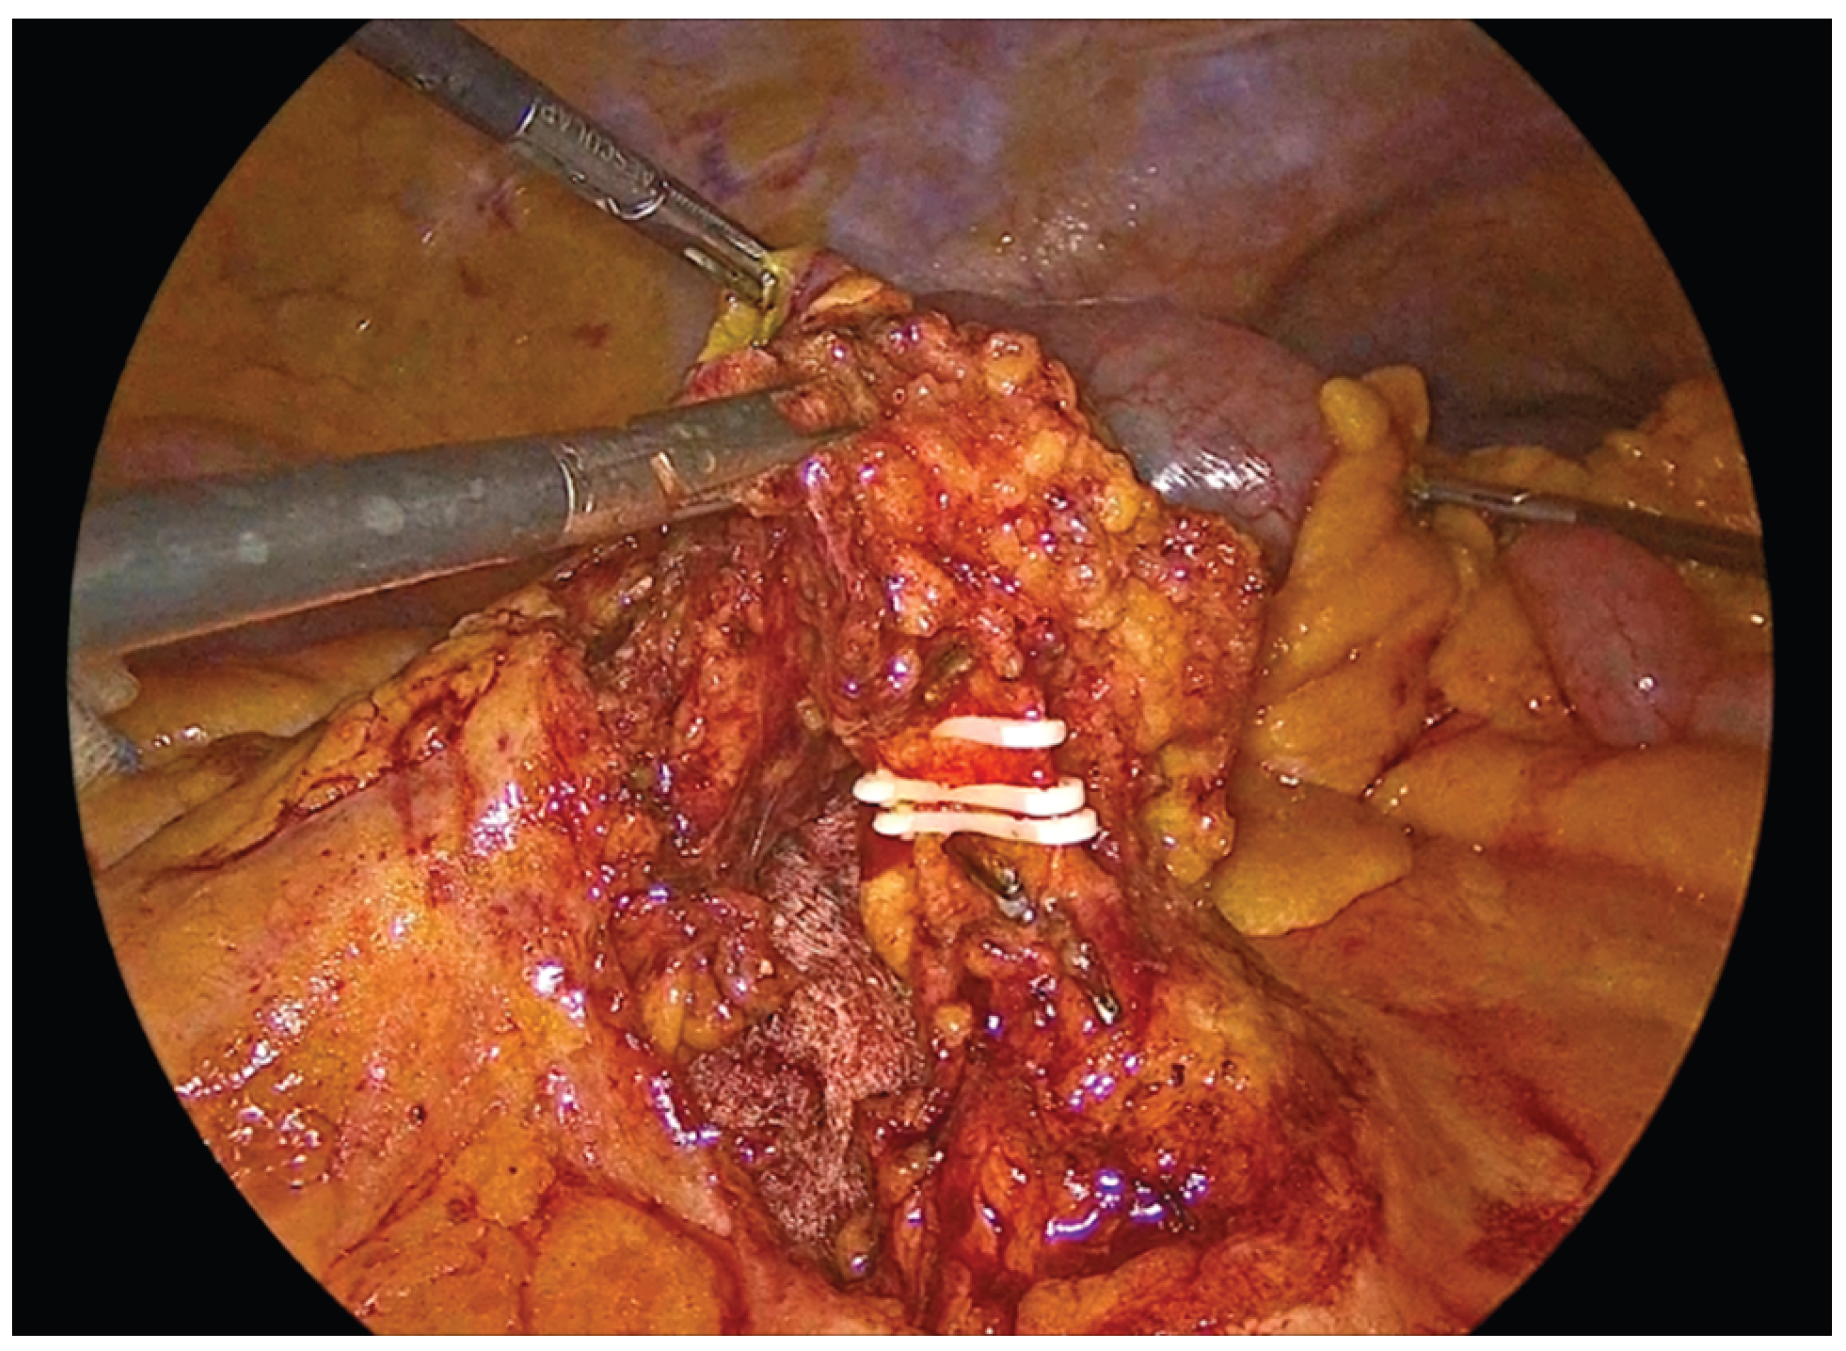

Dissection is performed using a medial-to-lateral approach. The ileocecal junction is first identified, followed by exposure of the ileocolic pedicle. The mesenteric peritoneum is incised using an ultrasonic scalpel and the avascular plane between the mesocolon and the retroperitoneum is developed through a combination of blunt and sharp dissection. Dissection proceeds laterally along the embryologic plane following the Told’s fascia. Once the dissection is completed the ileocolic vessels are divided between hemolock clips at their origin just off and below the duodenum. Cranially the dissection follows the anterior mesenteric vein up to the middle colic vein where the right branches of middle colic vessels are divided between hemolock clips. The dissection then proceeds from above through the gastrocolic ligaments with the patient in reverse Trendelenburg position. Care must be taken to find the correct plane through the lesser sac and keep the mesogastrium intact. The dissection then follows the transverse colon up to the hepatic flexure and then caudally towards the cecum, while mobilizing the ascending colon from the lateral peritoneal attachments.

Figure 1. Identification of the Ileocolic pedicle.